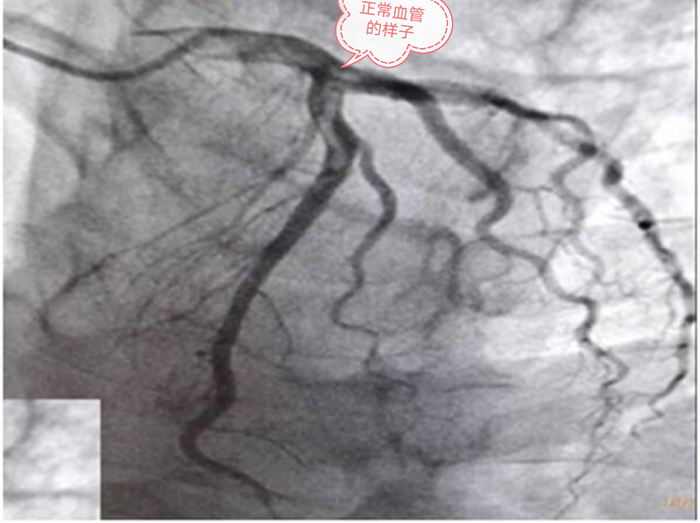

文章插图

左侧两根血管

冠状动脉也就是心脏动脉有三个大血管 , 右侧有一根的叫右冠 , 左侧有两根 , 左前方叫前降支 , 左后方叫回旋支;在左前方和左后方这两个血管其实还有一个根 , 那就是左主干 。 也就是左主干这个最大的心脏血管 , 发出两个大血管 , 分别是前降支和回旋支 。